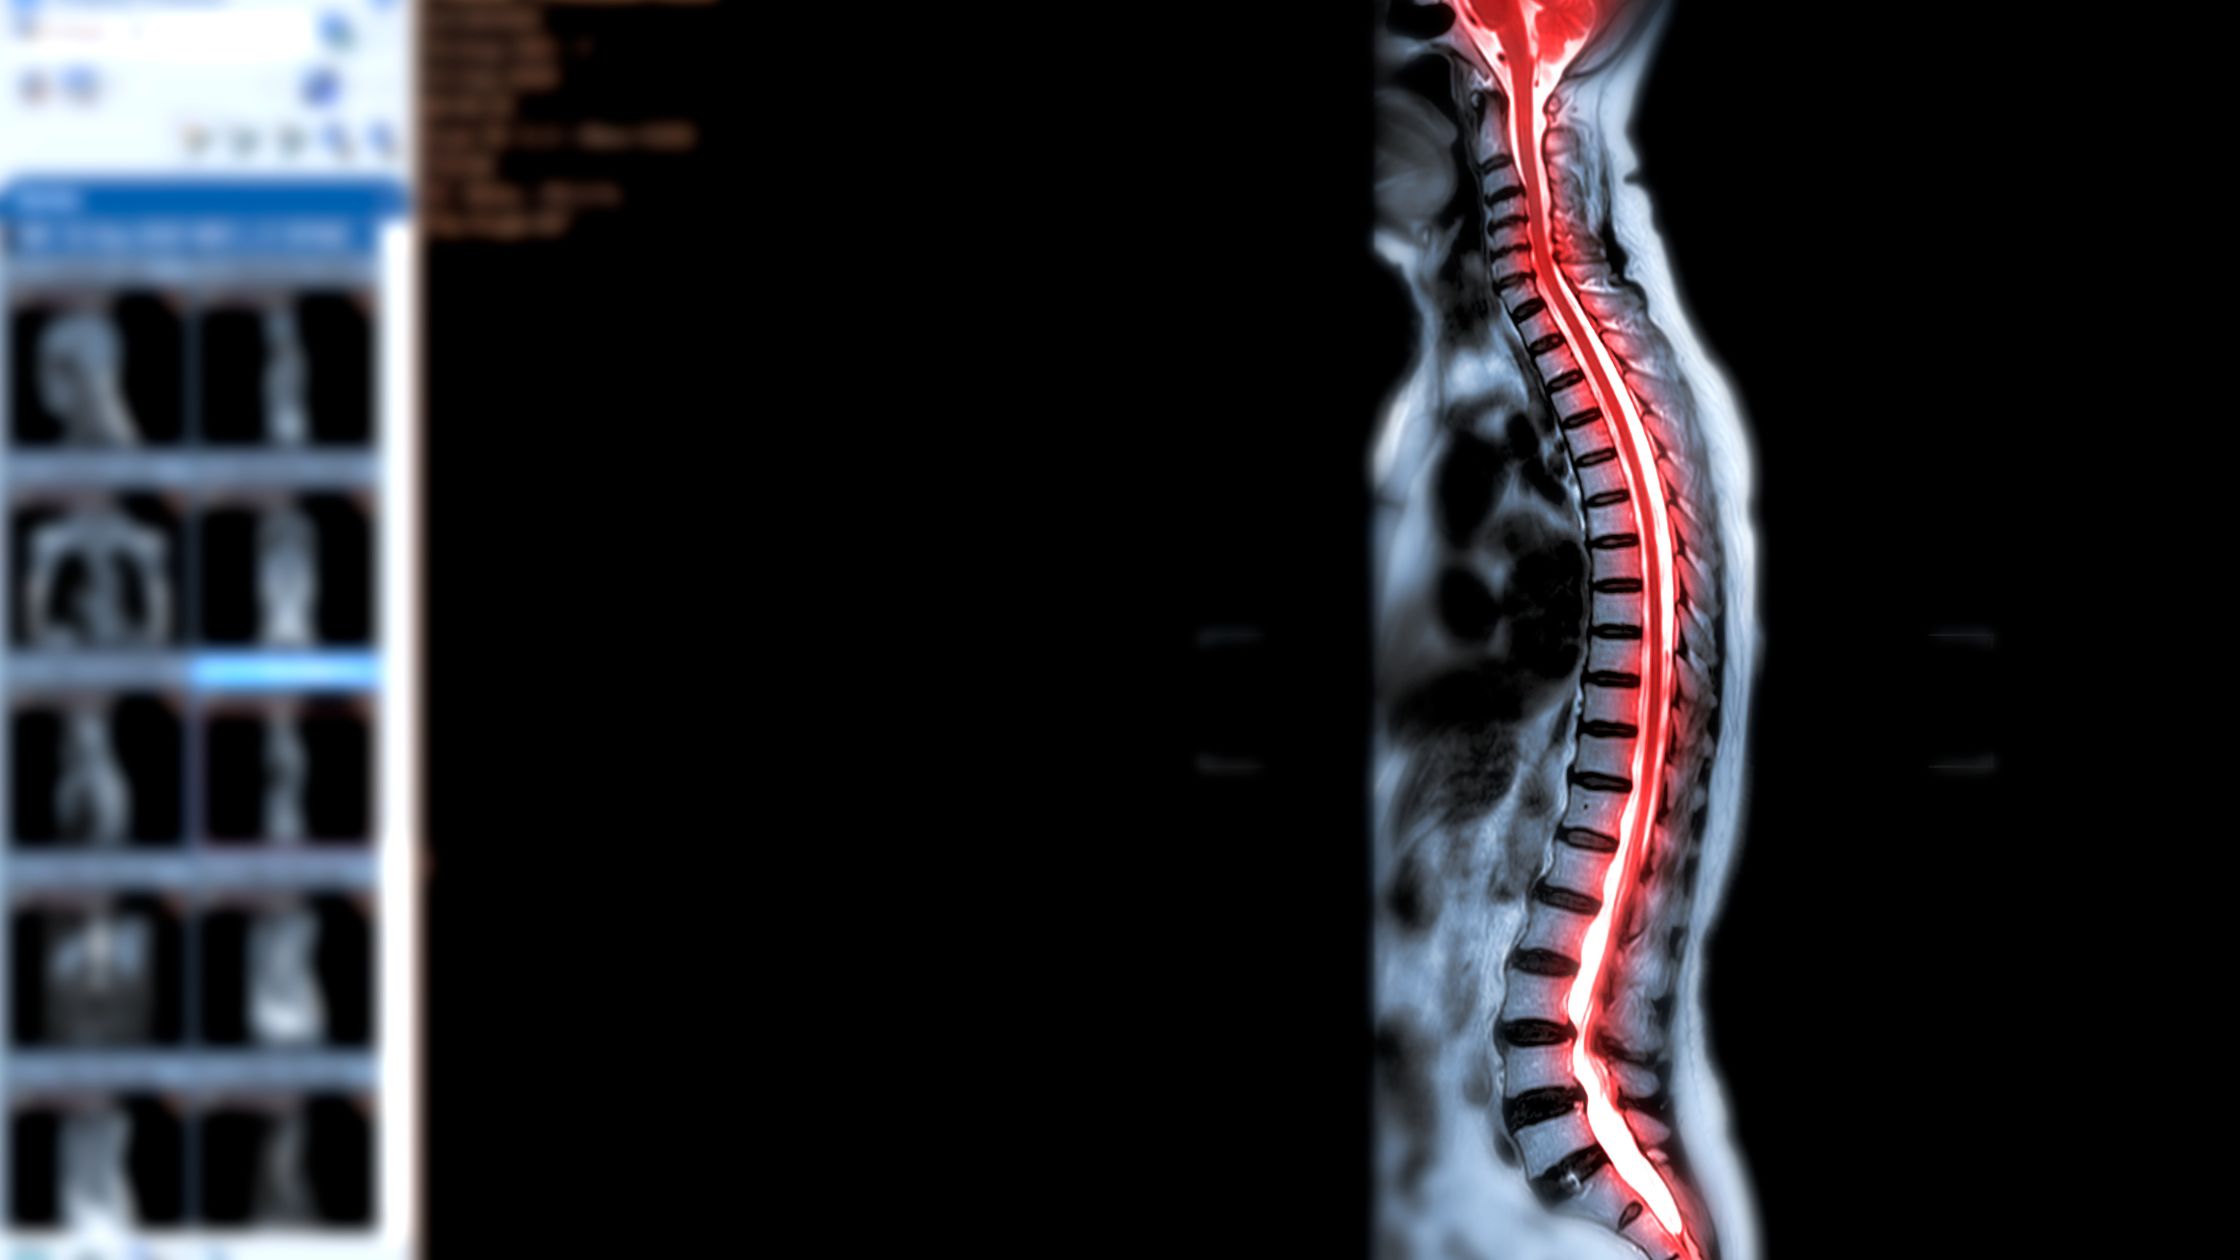

استشاري جراحة المخ والأعصاب و العمود الفقري

دكتوراة جراحة المخ و الاعصاب و العمود الفقري جامعة القاهرة

أستاذ و استشاري جراحات المخ و الاعصاب والعمود الفقري بالقصر العيني

زمالة جامعة جرايسفيلد الألمانية في مناظير المخ و العمود الفقري

عضو الجمعيه الأوروبية لجراحات العمود الفقري

خدمات عيادة د/إبراهيم الشال